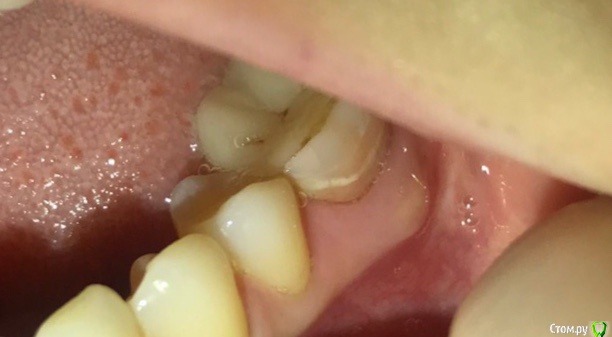

Евагэпс Опубликовано 15 ноября, 2018 Поделиться Опубликовано 15 ноября, 2018 Обнаружила у себя на десне возле депульпированного зуба с керамической вкладкой белесое образование в виде шишки. При надавливании болезненное. Температура 37.1, но нахожусь в тропическом климате, у моей подруги тут такая же. Повреждений десны не было.Вкладка стоИт три месяца.Прилагаю рентгеновский снимок зуба двухнедельной давности и сегодняшнее фото десны. Нахожусь на Шри-Ланке. Тут все оочень плохо с медициной. Прошу дистанционной помощи.Из лекарств с собой есть антибиотики, фурацилин и метрагил дента. Ссылка на комментарий

Neilrus Опубликовано 15 ноября, 2018 Поделиться Опубликовано 15 ноября, 2018 Обнаружила у себя на десне возле депульпированного зуба с керамической вкладкой белесое образование в виде шишки. При надавливании болезненное. Температура 37.1, но нахожусь в тропическом климате, у моей подруги тут такая же. Повреждений десны не было.Вкладка стоИт три месяца.Прилагаю рентгеновский снимок зуба двухнедельной давности и сегодняшнее фото десны. Нахожусь на Шри-Ланке. Тут все оочень плохо с медициной. Прошу дистанционной помощи.Из лекарств с собой есть антибиотики, фурацилин и метрагил дента.Начинается гнойный процесс в области где корни расходятся. По возвращению домой зуб необходимо удалить, к сожалению, чтобы не удалять там где вы находитесь можете "задавить" процесс антибиотиками Ссылка на комментарий

Евагэпс Опубликовано 15 ноября, 2018 Автор Поделиться Опубликовано 15 ноября, 2018 Начинается гнойный процесс в области где корни расходятся. По возвращению домой зуб необходимо удалить, к сожалению, чтобы не удалять там где вы находитесь можете "задавить" процесс антибиотикамиЭто то, что черное на снимке между корней? А на фото внешнее проявление этого? Антибиотки начала пить сегодня утром.Я этот снимок специально делала перед отъездом, так как недавно ставила вкладку. И врач отпустил меня со спокойной душой( Ссылка на комментарий

DmitrySH Опубликовано 16 ноября, 2018 Поделиться Опубликовано 16 ноября, 2018 Диагноз: периодонтит Ссылка на комментарий

Neilrus Опубликовано 16 ноября, 2018 Поделиться Опубликовано 16 ноября, 2018 Через 3 месяцамноговато, даже если сейчас задавите АБ, то через месяц может опять "раздует"...серфинг, все делаДа, периодонтит Ссылка на комментарий